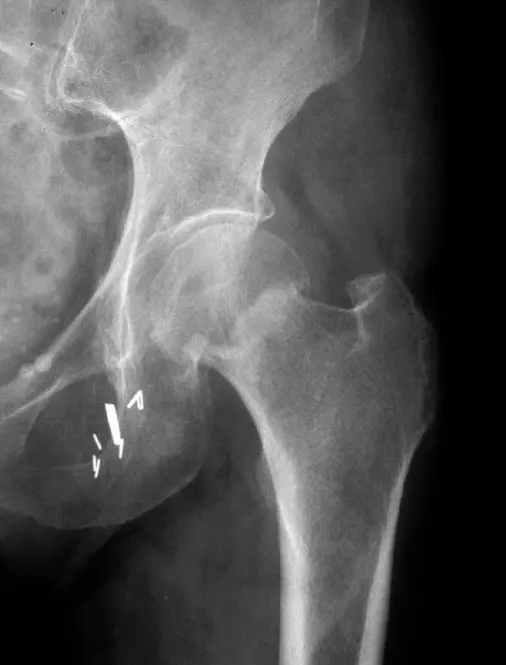

- Site: NeckâŻLtâŻfemur â intraâcapsular

- Type: Simple

- Fracture line: Transverse

- Displacements: Valgus / impaction

- Special issues: Stable; has vascular clips; AVN depends on age